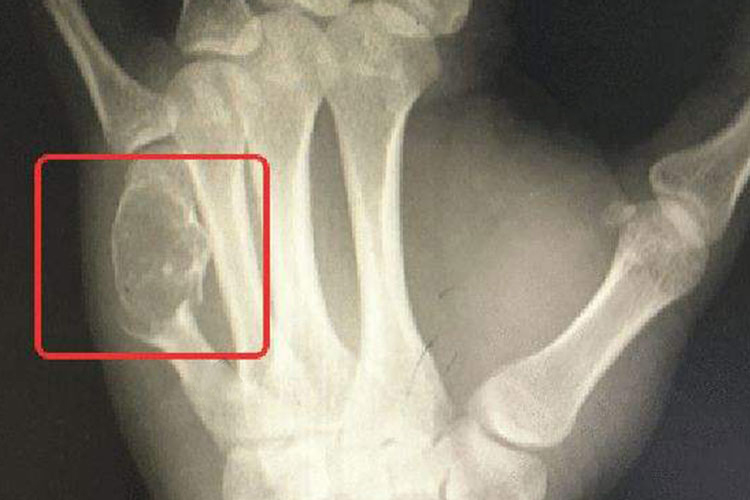

骨癌长刺患者可表现为患部疼痛,关节与肢体有局部肿块及肿胀。骨癌长刺的病因至今未明,常联合应用手术、化疗和放疗治疗。

骨癌长刺患者可表现为患部疼痛,关节与肢体有局部肿块及肿胀,患部关节与肢体运动受限制。同时患部皮肤会有不同程度的溃烂,肢体远端会有麻木感,可发生病理性骨折或变形,伴有食欲减低、体重减轻、发烧等症状。